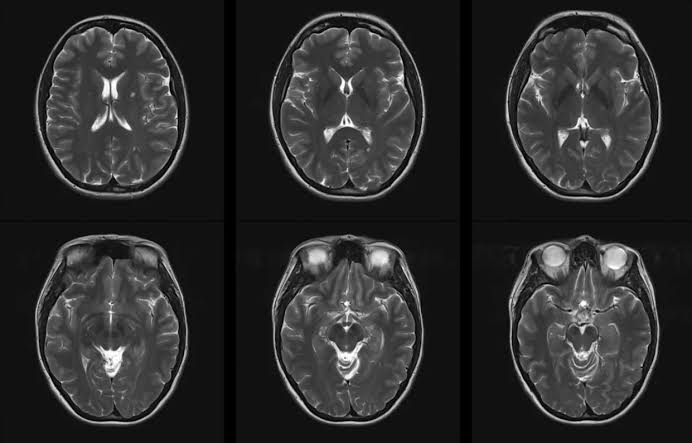

Air pollution's reputation as a "silent killer" is well-earned. New research indicates that dirty air is also linked to raising the risk of developing...